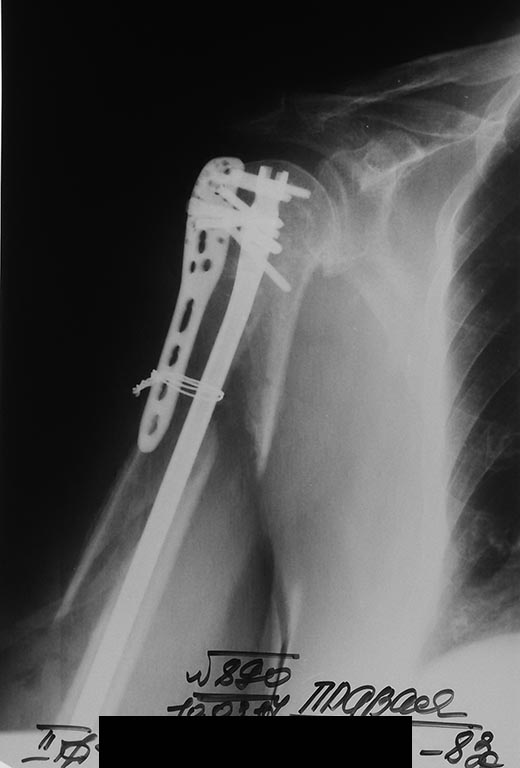

Судя по снимку, пластина держится за головку плечевой кости. Винты в хвосте пластины висят в воздухе, так как линия перелома прошла через них. На послеоперационных рентгенограммах хвост так же отстоит?

В любом случае, БИОС плечевой кости может оказаться скомпрометированным нестабильностью проксимальной фиксации. Вариант проведения блокирующего винта через пластину сомнителен из-за диаметра отверстий под винты. Есть ли гвозди с 3,5 мм проксимальными винтами? В противном случае будет люфт при ротации плеча.

Таков результат. Раны зажили первично. Пациентка выписана без иммобилизации. Буду наблюдать в динамике. Жду комментариев.Коллеги. Спасибо всем за советы.

А можно более развернуто? Что как сделали?

По этому снимку не радует большой диастаз.